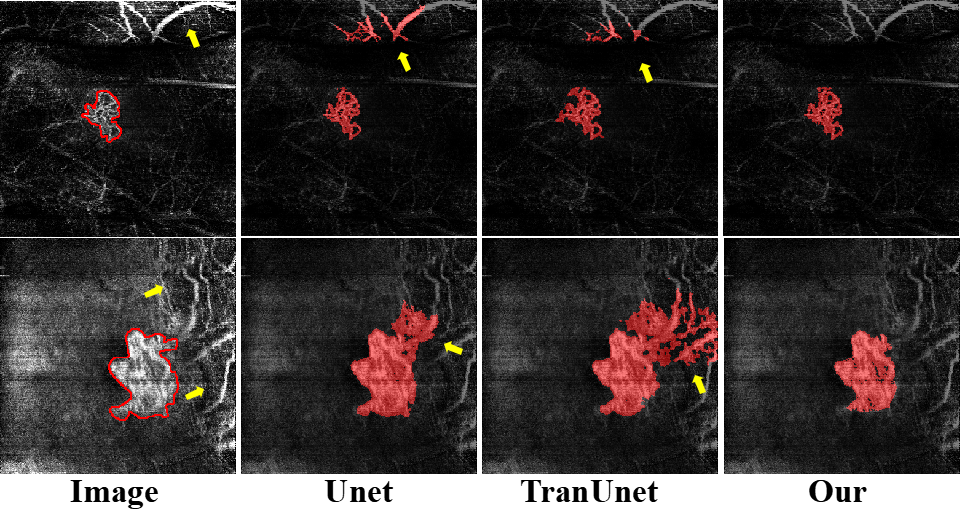

Figure 7: Qualitative comparisons of MTG-Net with other methods are shown. Red indicates the vessel segmentation results from competing methods, while red lines show the region contours from the ground truth. Yellow highlights the segmentation results produced by different methods.

We perform comparative analysis to demonstrate the superior performance of our method across the mixed dataset. Fig. 7 provides quantitative comparisons of region and vessel segmentation results with respect to different state-of-the-art methods. By integrating global and local information through graph neural networks and multi-task learning, MTG-Net shows excellent performance particularly in managing CNV scale variations. As shown in rows 5-8 in Fig. 7, compared to other networks, MTG-Net demonstrates its effectiveness in coping with CNV lesions of various scales. Additionally, as shown in the 2th2{th} and 4th4{th} rows of the vessel segmentation results, as well as the 6th6{th} and 8th8{th} rows of the region segmentation results, the use of uncertainty estimation loss allows MTG-Net to accurately delineate lesion boundaries even in ambiguous regions. Unlike other networks, MTG-Net also shows reliability in avoiding over-segmentation when dealing with artifacts and noise that resemble CNV. Finally, it is important to note that the segmentation results in Fig. 7 are derived from multiple devices. Despite the varying data conditions across them, MTG-Net consistently shows robust segmentation performance, indicating its superior generalization capability.